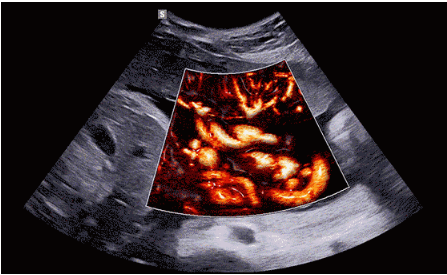

CrystalLive?是三星最新的超聲成像引擎,同時(shí)增強(qiáng)了2D圖像處理能力、3D渲染能力和彩色信號(hào)處理能力,能夠在復(fù)雜情況下提供出色的圖像性能,具備檢測外周血管、微循環(huán)血流的能力。